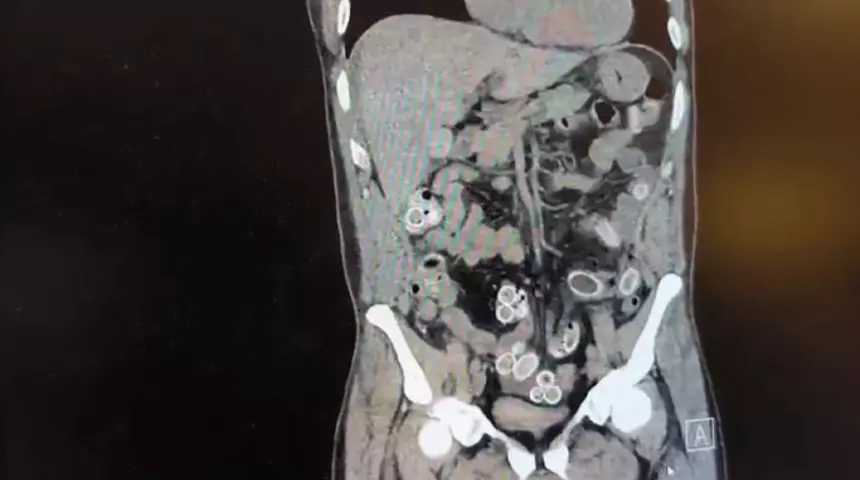

Tomografisi çekilen Cüneyt Ç.’nin mide ve bağırsaklarında yabancı madde bulunduğu tespit edildi. Hastane yetkililerinin bilgi vermesi üzerine Beşiktaş Asayiş Büro Amirliği ekipleri tarafından konuyla ilgili çalışma başlatıldı. Ameliyata alınan Cüneyt G.’nin mide ve bağırsaklarından kapsül halinde 49 adet esrar macunu çıkarıldı.

Fas’tan yaklaşık 3 bin kilometre uzaklıktan uçakla Türkiye’ye gelen Cüneyt G., 2 gün sonra karın ağrısı şikayetiyle Fulya’daki özel bir hastaneye başvurdu. Yapılan muayenenin ardından Cüneyt G.’nin tomografisi çekildi. Şüphelinin mide ve bağırsaklarında yabancı madde tespit edilmesi üzerine hastane yetkilileri durumu polis ekiplerine bildirdi.

Doktorların değerlendirmesi sonrası ameliyata alınan Cüneyt Ç.’nin bağırsaklarından, toplam ağırlığı 259,7 gram olduğu öğrenilen 49 esrar macunu çıkarıldı. Şüpheliye ait 1 adet cep telefonu da hastane yetkilileri tarafından polis ekiplerine teslim edildi.